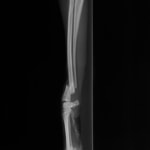

術前レントゲン

術後レントゲン

ペルシャ猫 11ヶ月齢 雄

他院にて左大腿骨遠位の成長板骨折(salter-harrisⅠ型)が認められており、治療相談を目的として来院。当院にて、キルシュナーワイヤーを用いたピンニングにより骨折部位の整復を行いました。術後の経過は良好で、現在も経過観察中です。